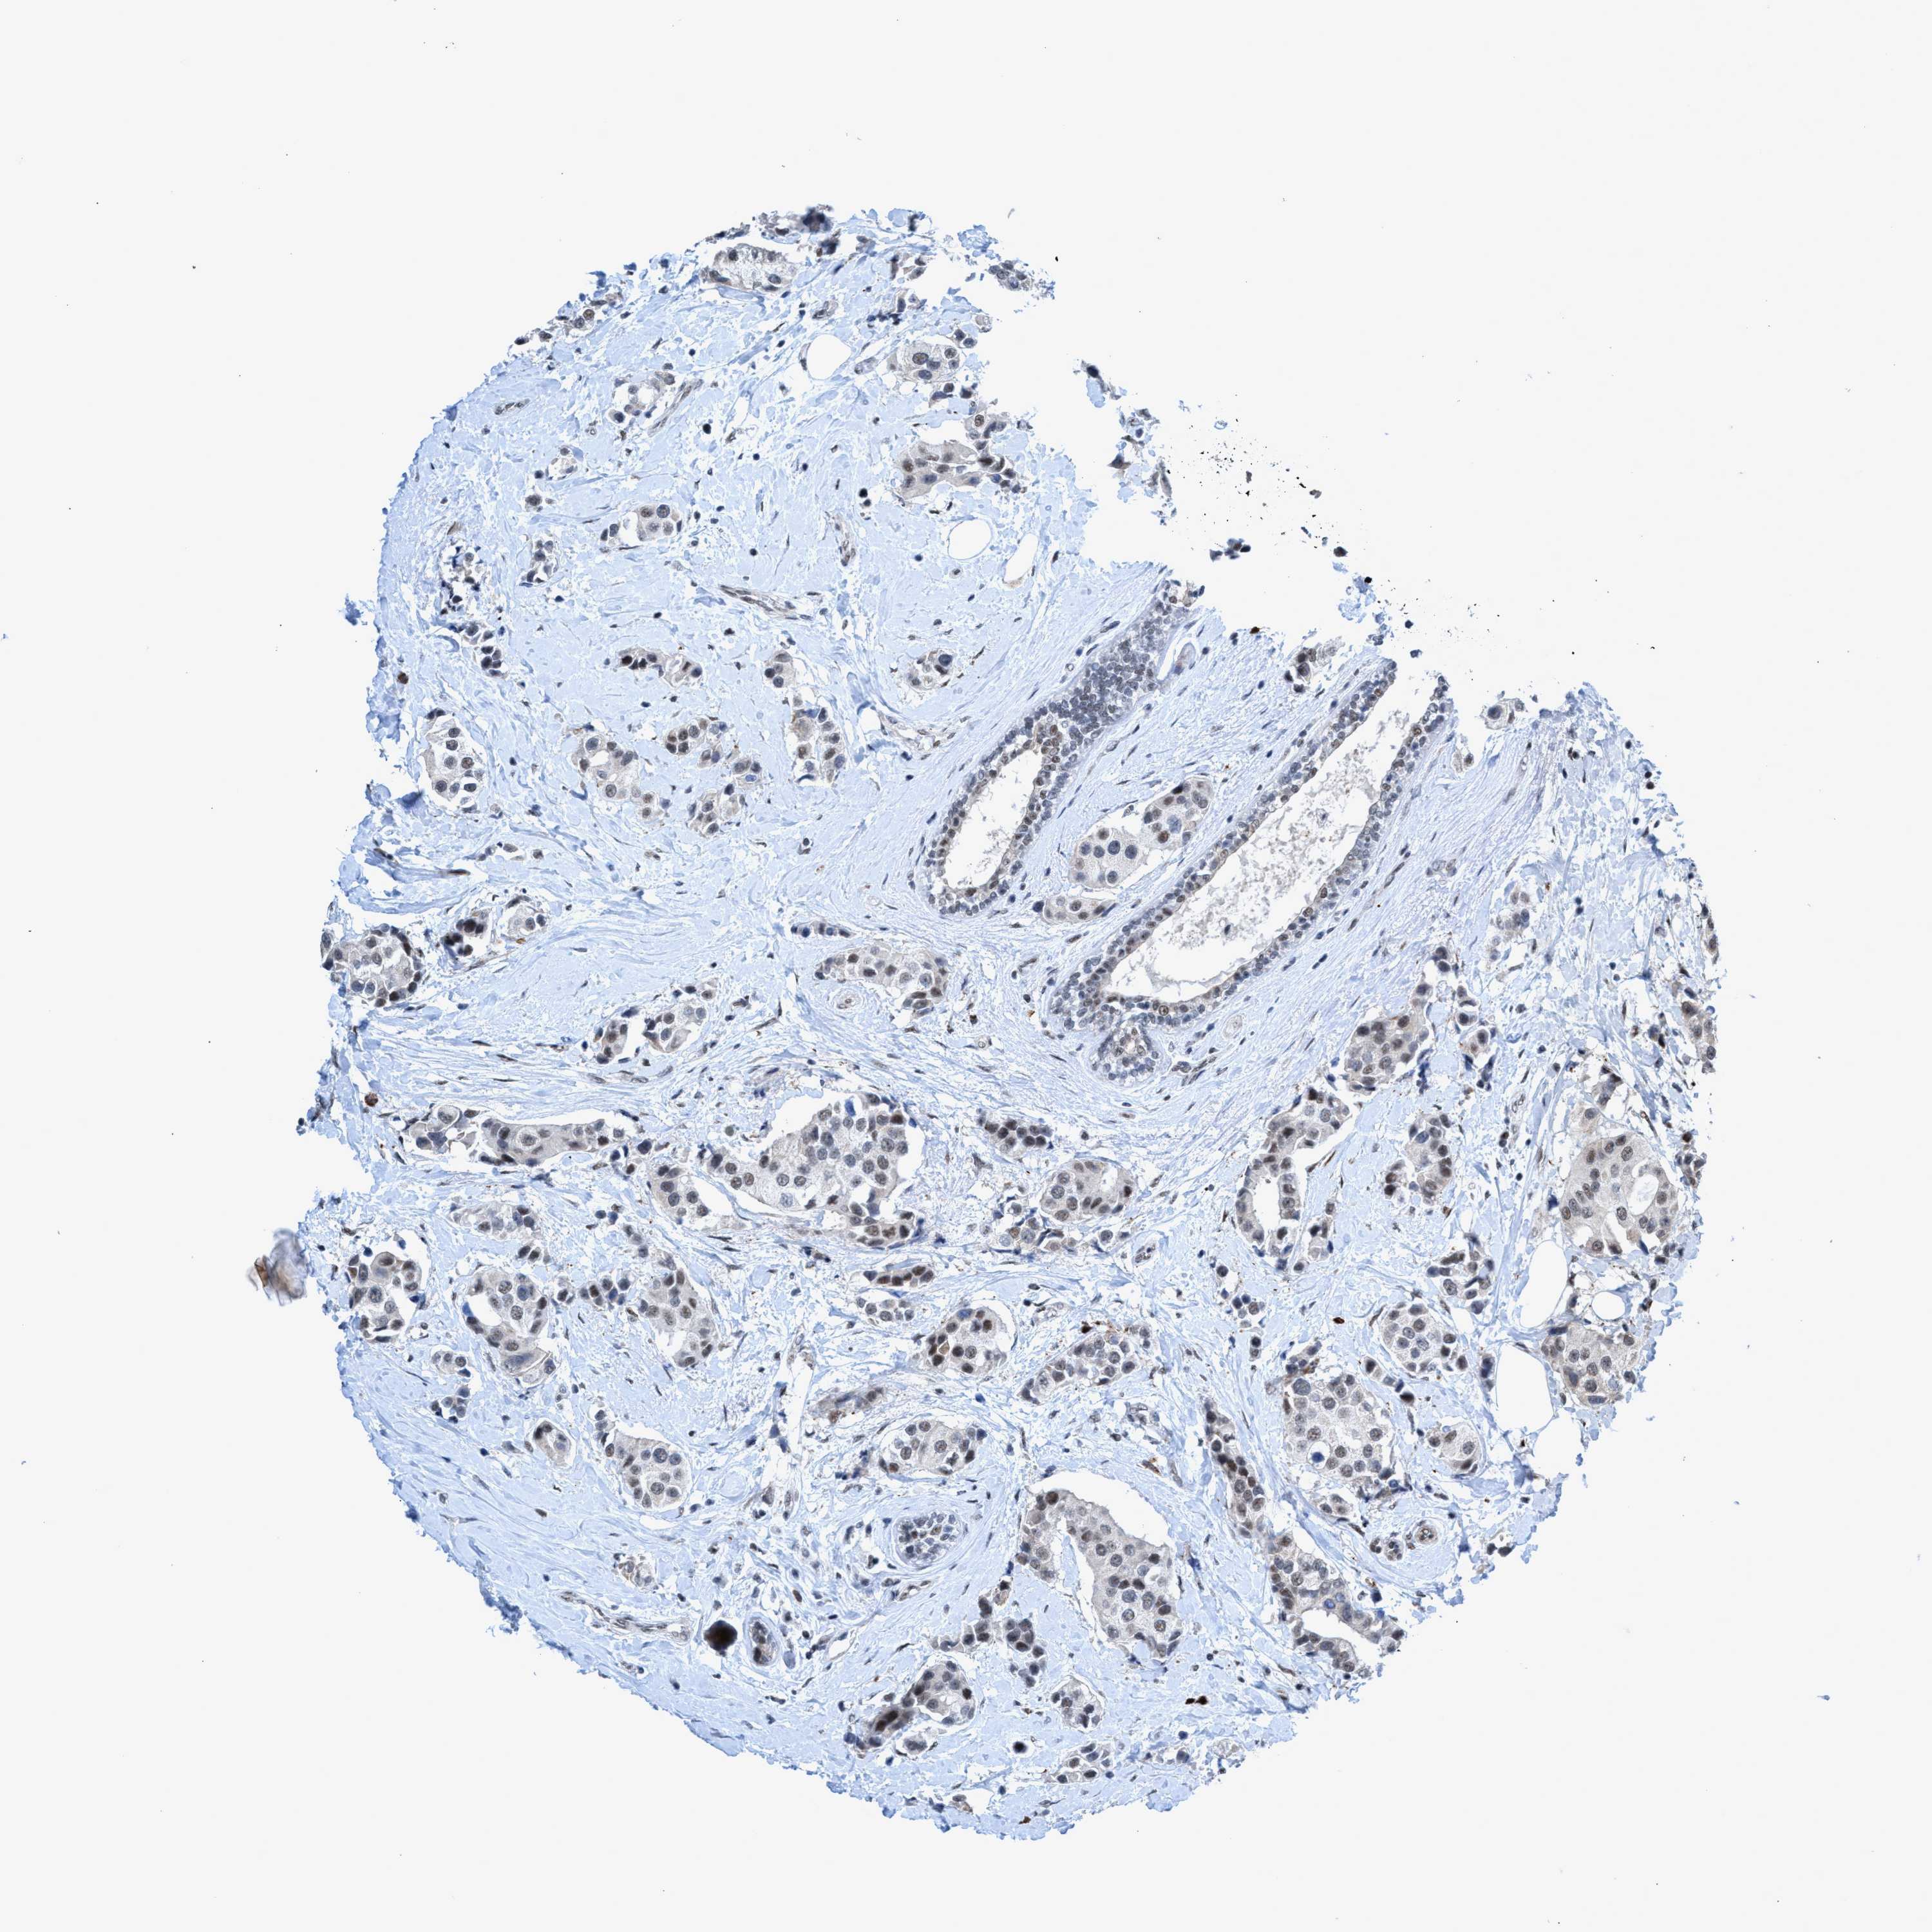

CANCER BREAST CANCER Show tissue menu

BRCA TCGA BRCA VALIDATION PROTEIN EXPRESSION